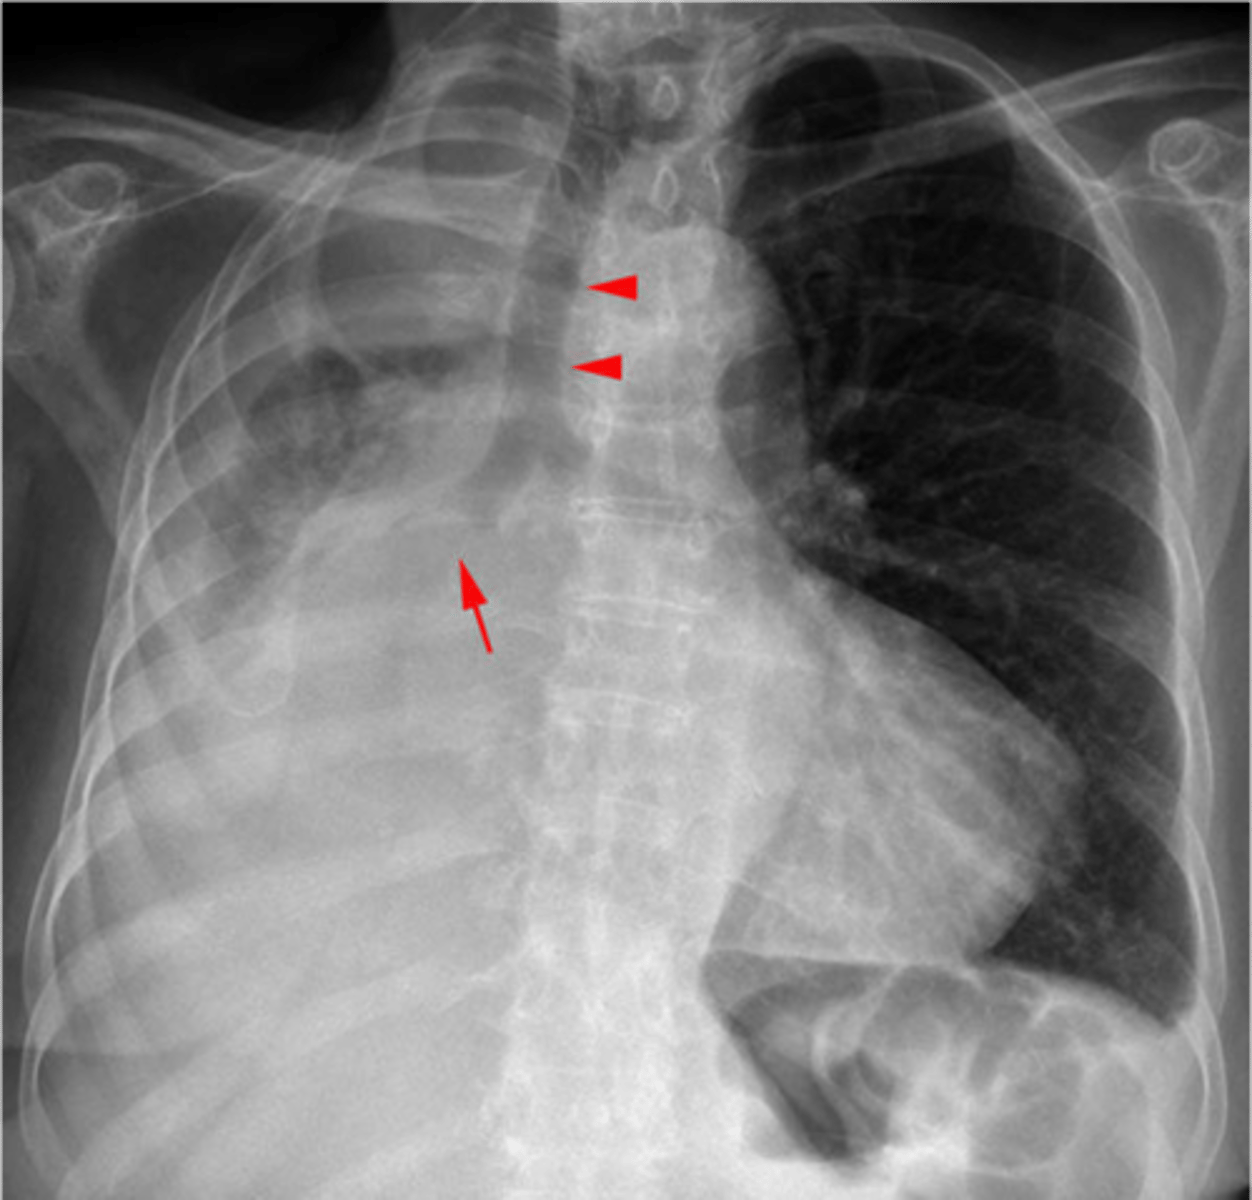

Pneumomediastinum (mediastinal emphysema)

Pneumomediastinum

Diaphragmatic rupture

Diaphragmatic rupture

Diaphragmatic hernia

congestive heart failure

congestive heart failure